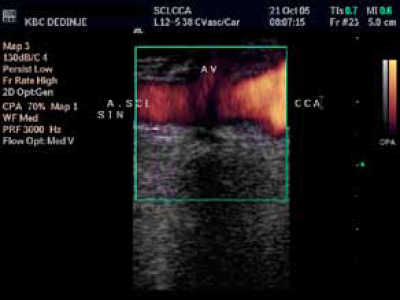

By pass carotico subclavialis. Uredan kontrlni Color Duplex nalaz i spektralna analiza.